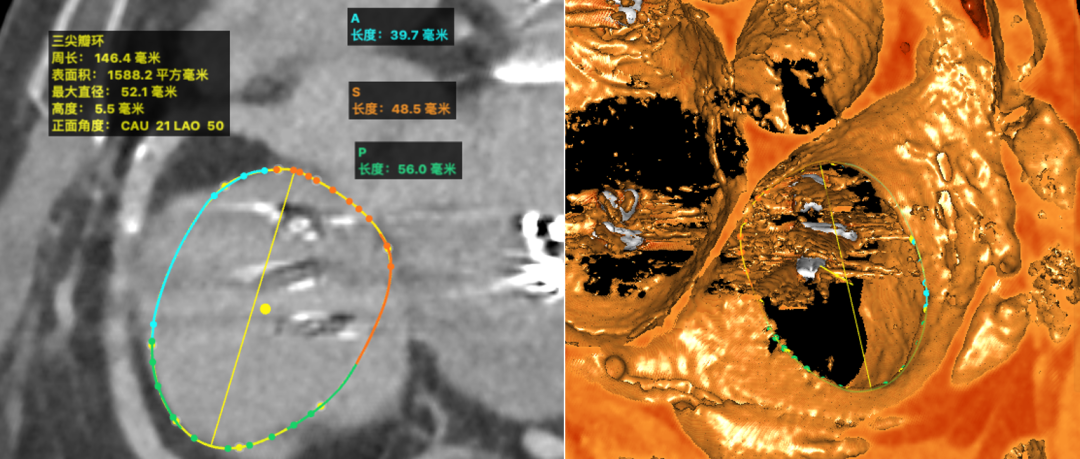

术前CT影像检查

提示三尖瓣环严重扩张

患者,女性,83岁,因房颤、重度二尖瓣反流于2017年10月行经导管二尖瓣叶钳夹术(MitraClip)和左心耳封堵术,2019 年5月因二尖瓣反流复发、三尖瓣重度反流再次行经导管二尖瓣叶钳夹术(MitraClip)和三尖瓣叶钳夹术(TriClip),今年因三尖瓣反流复发,伴随肾功能损害和肝硬化入院,心超示双房及右室增大,极重度三尖瓣反流伴中度二尖瓣反流及。CT提示三尖瓣扩大(三尖瓣平均直径: 48.7mm)。EuroScoreII评分8.6分,经过心脏团队的术前讨论,认为外科手术高危,需要进一步手术进行治疗。